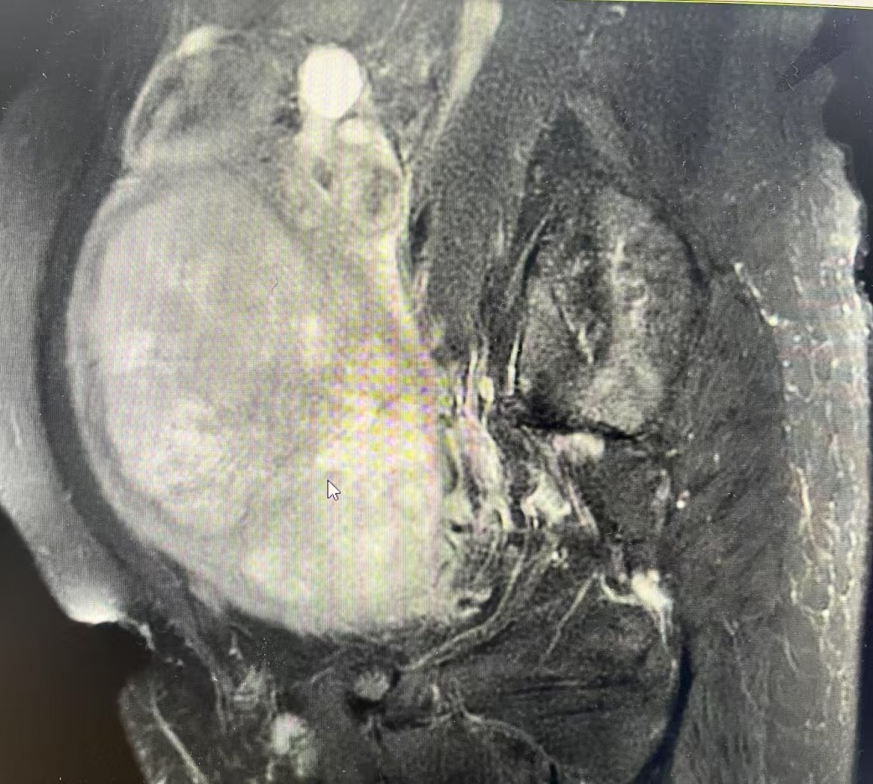

检查结果令人扼腕:王阿姨的盆腔内有一个巨大的肿瘤,考虑为子宫恶性肿瘤。充分评估后我们为她实施了“经腹全子宫+双侧附件切除术”,术后病理诊断揭开了真相——高级别子宫内膜间质肉瘤,一种恶性程度较高的子宫恶性肿瘤。由于发现较晚,肿瘤已经长得非常大,错过了最佳的早期治疗时机。

认识“子宫肉瘤”——隐匿的杀手

王阿姨所患的“高级别子宫内膜间质肉瘤”属于子宫肉瘤的一种。这是一种起源于子宫肌层或子宫内膜间质的恶性肿瘤,相对于常见的子宫内膜癌,它更为罕见,但恶性程度更高,进展更快,早期症状也不典型。

温馨提示:手术实况图像可能引起不适,非专业人士请勿点击浏览。